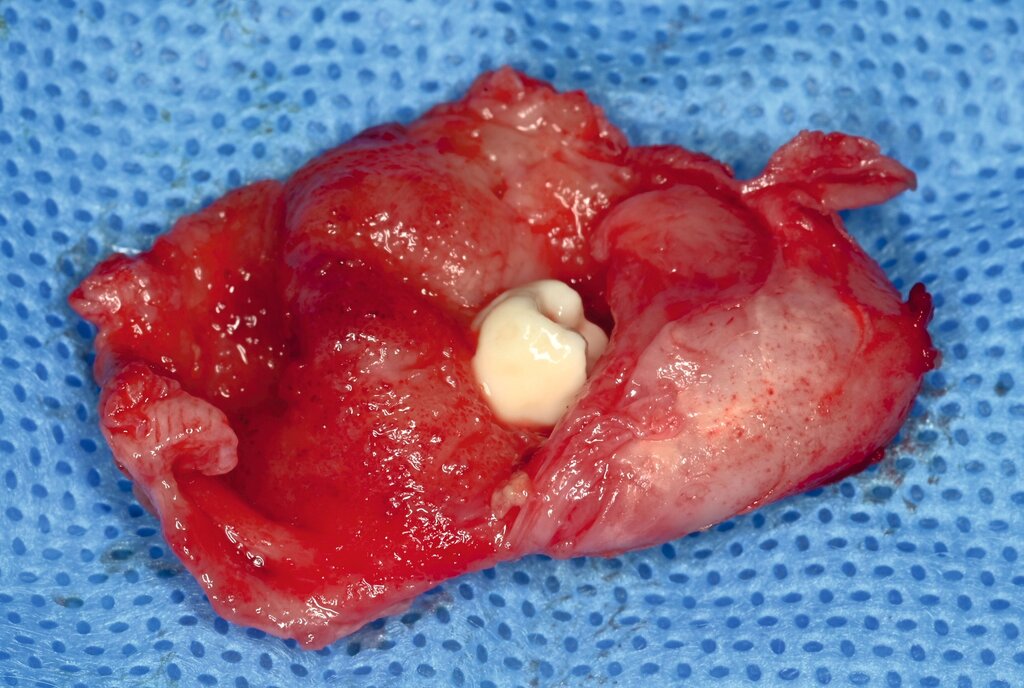

Hinzu kommen erhebliche Defizite in der Fort- und Weiterbildung: Eine fachzahnärztliche Spezialisierung findet praktisch nicht statt, was sich im fachlichen Austausch mit den lokalen Kolleginnen und Kollegen widerspiegelt. Die Zahnmedizin befindet sich vielfach noch in einer kurativen Phase, während westliche Gesundheitssysteme längst präventiv ausgerichtet sind. Diese strukturellen Defizite zeigen sich unmittelbar im klinischen Alltag. Der Stellenwert der Zahngesundheit ist – auch bedingt durch die langjährige Krisensituation – deutlich geringer als in westlichen Ländern. In Kombination mit einer zuckerreichen Ernährung weisen bereits Kinder häufig ausgeprägte kariöse Läsionen auf. Die unbehandelten Entzündungen und der oft frühzeitige Zahnverlust führen zu funktionellen Einschränkungen und erschweren spätere chirurgische Eingriffe erheblich.

Der Behandlungsschwerpunkt des Einsatzes lag auf der operativen Versorgung von Kindern mit Lippen-Kiefer-Gaumenspalten, großen zystischen Läsionen sowie dysgnathiechirurgischen Fragestellungen. Gerade bei den LKG-Patientinnen und -Patienten zeigte sich die enge Verzahnung zwischen Zahnmedizin, Kieferorthopädie und Chirurgie – und gleichzeitig die strukturellen Limitationen der Behandlung in Palästina. Häufig stellten sich die Kinder mit ausgeprägter Karies, entzündlichen Veränderungen und einer fehlenden kieferorthopädischen Vorbereitung vor. Zudem fehlt eine strukturierte interdisziplinäre Zusammenarbeit, etwa mit der HNO-Heilkunde und der Logopädie.